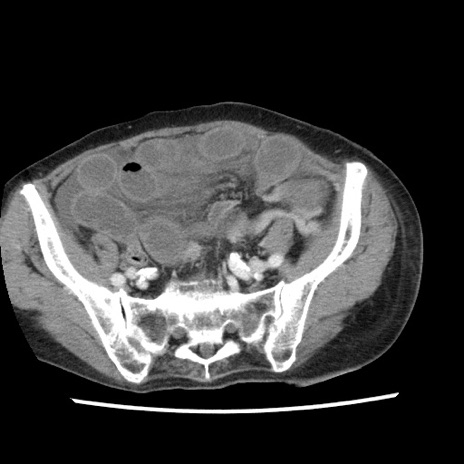

症例1(横断像)

【症例】80歳代女性

【主訴】腹痛

【現病歴】8時間前から腹痛あり来院。

【既往歴】糖尿病、脂質異常症、子宮体癌にて子宮全摘術

【身体所見】意識清明・会話良好だが腹痛で苦悶様、全腹部にわたって反跳痛と圧痛あり

【データ】WBC 13600、CRP 0.14、LDH 224、CK 90